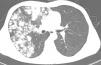

A 34-year-old male non-smoker was admitted for incidentally found pulmonary nodules. He had previously been misdiagnosed with “pulmonary tuberculosis”. Computed tomography (Fig. 1) revealed numerous round nodules of varying sizes and densities, some with a characteristic “popcorn” calcification, diffusely distributed primarily in the upper and middle lobes of the right lung. The patient underwent a thoracotomy, during which many hard, grayish-white nodules measuring 0.3–3cm in diameter were observed. The postoperative pathological results confirmed the diagnosis of pulmonary chondromatous hamartoma (PH) which primarily comprises cartilage. At his 4-year follow-up, the patient remained asymptomatic with no evidence of recurrence. PH is the most common benign tumor of the lung, characterized by solitary nodules on the periphery of the lungs, constituting 5–8% of all solitary pulmonary nodules.1 However, the PH nodules reported in this case exhibit a popcorn-like diffuse distribution, which is extremely uncommon. Therefore, identification of pulmonary hamartomas is still necessary for cases involving multiple calcified nodules.